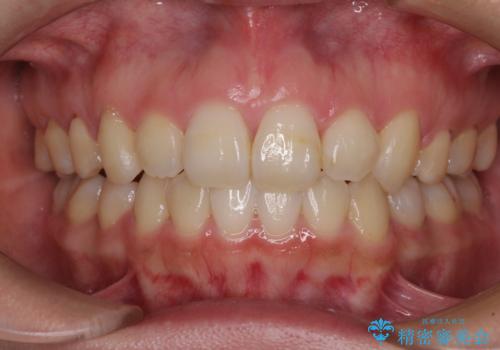

- 前歯や奥歯の虫歯を放置しており、それらの治療を契機に真っ白な歯にしたいとのことで来院された患者様です。

不自然なくらい真っ白にしたいとのことでしたので、透明感のないフルジルコニアクラウンを用いて補綴することとしました。